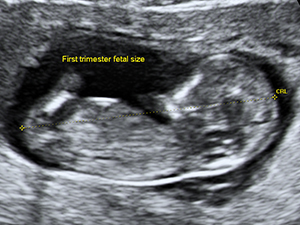

懷孕12週的胎兒頭臀長